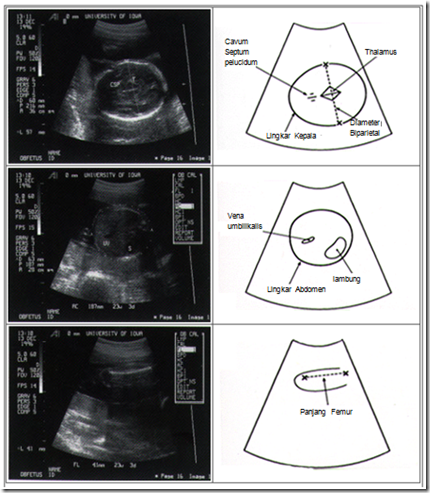

Keterangan gambar 2:

• (atas) Biometri BPD yang ditandai dengan x …………….x serta lingkar kepala.

• (tengah) lingkar abdomen

• (bawah) Biometri Panjang Femur yang ditandai dengan x ……….x